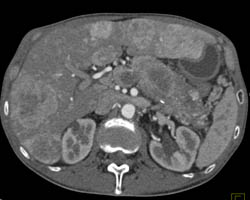

Hepatoma in Patient With Glycogen Storage Disease